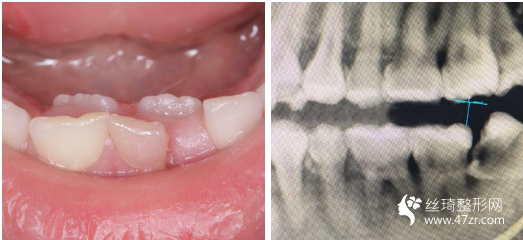

3.武漢愛(ài)齒爾口腔門(mén)診部張郭龍主治醫(yī)師案例展示

一直以來(lái),我算是一個(gè)對(duì)自己要求比較高的人,見(jiàn)不得自己有任何的瑕疵,就連牙齒也不行。 所以在我開(kāi)啟牙齒矯正路途前的三個(gè)月里,我托了較為多人進(jìn)行行業(yè)摸底(哈哈哈其實(shí)就是找個(gè)靠譜的醫(yī)生幫我做

很感謝我遇到了不錯(cuò)的醫(yī)生,在這方面臨床經(jīng)驗(yàn)比較豐富,醫(yī)生說(shuō)我的矯治過(guò)程進(jìn)展的較為順利,矯正速度真的是較為快呢,牙齒不齊整體也在調(diào)整牙齒咬合狀態(tài)了?,F(xiàn)在笑的時(shí)候更加自信了,所以牙弄齊了以后我打算在做個(gè)美白,平時(shí)抽煙牙齒也很黃